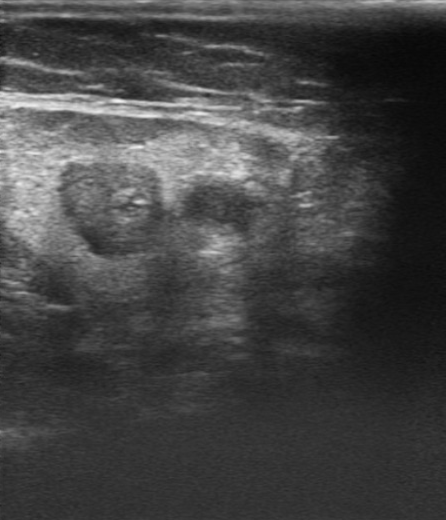

Ecografía de miembro inferior izquierdo: contenido hiperecogénico en todo el trayecto de la vena safena interna, no compresible. Sistema venoso profundo permeable sin datos de TVP (Imagen 2,3,4).

Tromboflebitis en todo el territorio de vena safena interna de miembro inferior izquierdo.